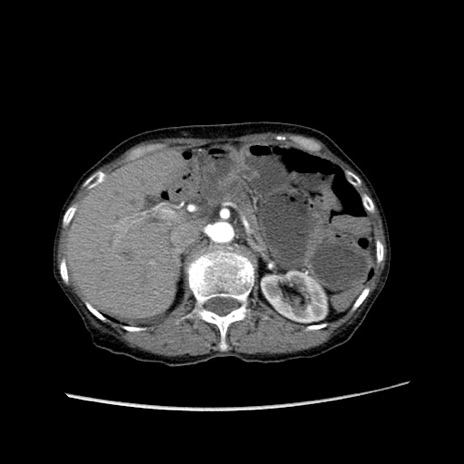

症例25(横断像)

【症例】80歳代女性

【主訴】胸のつかえ感

【現病歴】約9時間前に食後から胸のつかえた感じあり、嘔吐あり、来院。

【既往歴】胃癌(全摘)、胆摘、虫垂炎

【身体所見】心窩部に圧痛あり、反跳痛なし。

【データ】WBC 5700、CRP 0.05